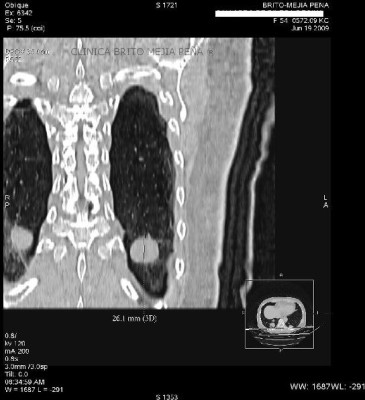

Tumor de esófago oblicua

Post Image